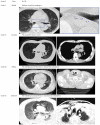

Methods: A total of 46 patients who were to undergo esophageal ESD were randomly assigned to receive either CO2 insufflation (CO2 group, n = 24) or air insufflation (Air group, n = 22). Computed tomography (CT) was carried out immediately after ESD and the next morning. Pain and abdominal distention were chronologically recorded using a 100-mm visual analogue scale (VAS). The volume of residual gas in the digestive tract was measured using CT imaging.

Results: The incidence of ME immediately after ESD in the CO2 group was significantly lower than that in the Air group (17% vs 55%, P = 0.012). The incidence of ME the next morning was 8.3% vs 32% respectively (P = 0.066). There were no differences in pain scores or distention scores at any post-procedure time points. The volume of residual gas in the digestive tract immediately after ESD was significantly smaller in the CO2 group than that in the Air group (808 mL vs 1173 mL, P = 0.013).